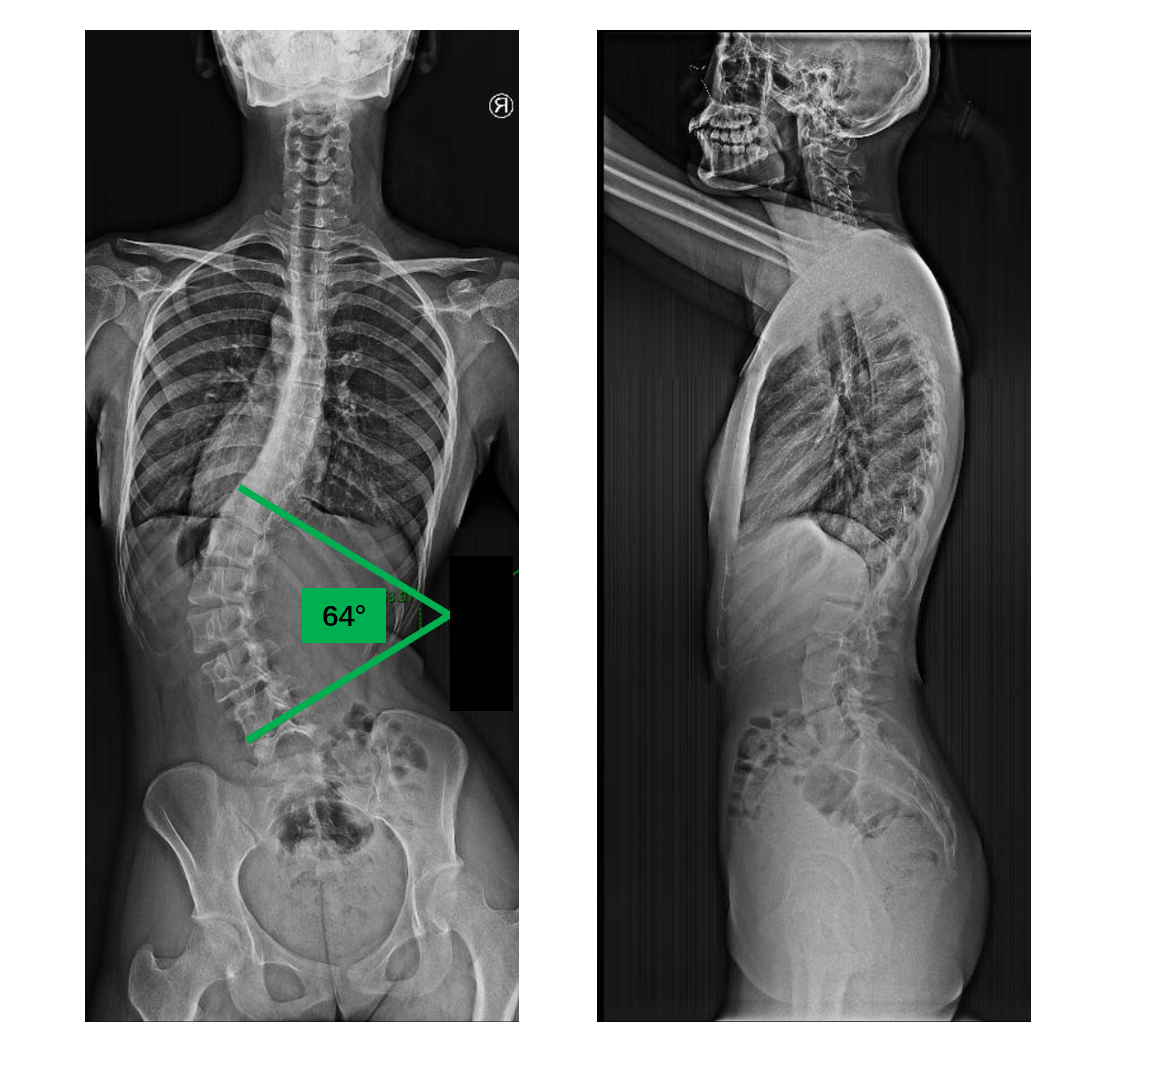

關(guān)注罕見病,綜合征性脊柱側(cè)彎:馬凡綜合征馬凡綜合征(Marfansyndrome)是一種影響結(jié)締組織的遺傳病,主要影響人體的心血管、眼睛和骨骼。從外觀上看,患有馬凡綜合征的人通常又高又瘦,手臂、腿、手指和腳趾的長度和比例顯著異于常人,胸骨向外突出或者凹陷,常合并脊柱側(cè)彎和扁平足。由于影響晶狀體、視網(wǎng)膜等結(jié)構(gòu),馬凡綜合征病人通常高度近視。最嚴重的并發(fā)癥是心血管系統(tǒng)病變,包括動脈夾層、動脈瘤、心臟瓣膜畸形,嚴重時可危及生命。心血管并發(fā)癥:動脈瘤:在血壓作用下菲薄的動脈壁膨出,類似于“爆胎”,多見于主動脈根部動脈夾層:動脈壁由多層結(jié)構(gòu)形成,最內(nèi)層出現(xiàn)破口后,血液涌入內(nèi)層和外層結(jié)構(gòu)之間,導致嚴重的胸背痛心臟瓣膜畸形:心臟瓣膜的結(jié)構(gòu)和功能異常,增加心臟做功,可以導致心衰骨骼并發(fā)癥:脊柱:脊柱側(cè)彎肋骨:肋骨發(fā)育畸形,導致胸骨突出或者凹陷扁平足:常見足痛眼睛并發(fā)癥:晶狀體異位視網(wǎng)膜病變:視網(wǎng)膜撕裂或者脫落風險增加青光眼、白內(nèi)障:年輕起病